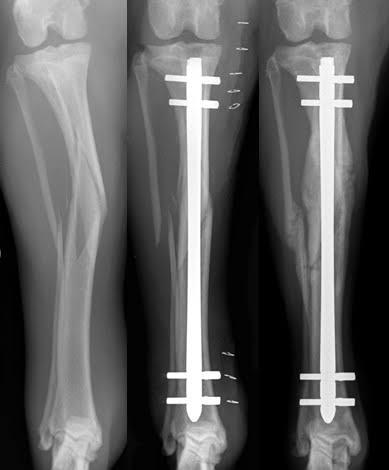

The centre runs 24 hrs emergency for accident cases managed by well equipped & trained staff all around the clock. Dr. Sagar Rane personally looks up all trauma cases & operates himself. All surgeries one done under C-ARM (scan) machine. So perfect results are achieved. He does vascular surgery /repair himself.

Under C-ARM all surgeries done through key hole incision and under bone scan control which gives 100% results.